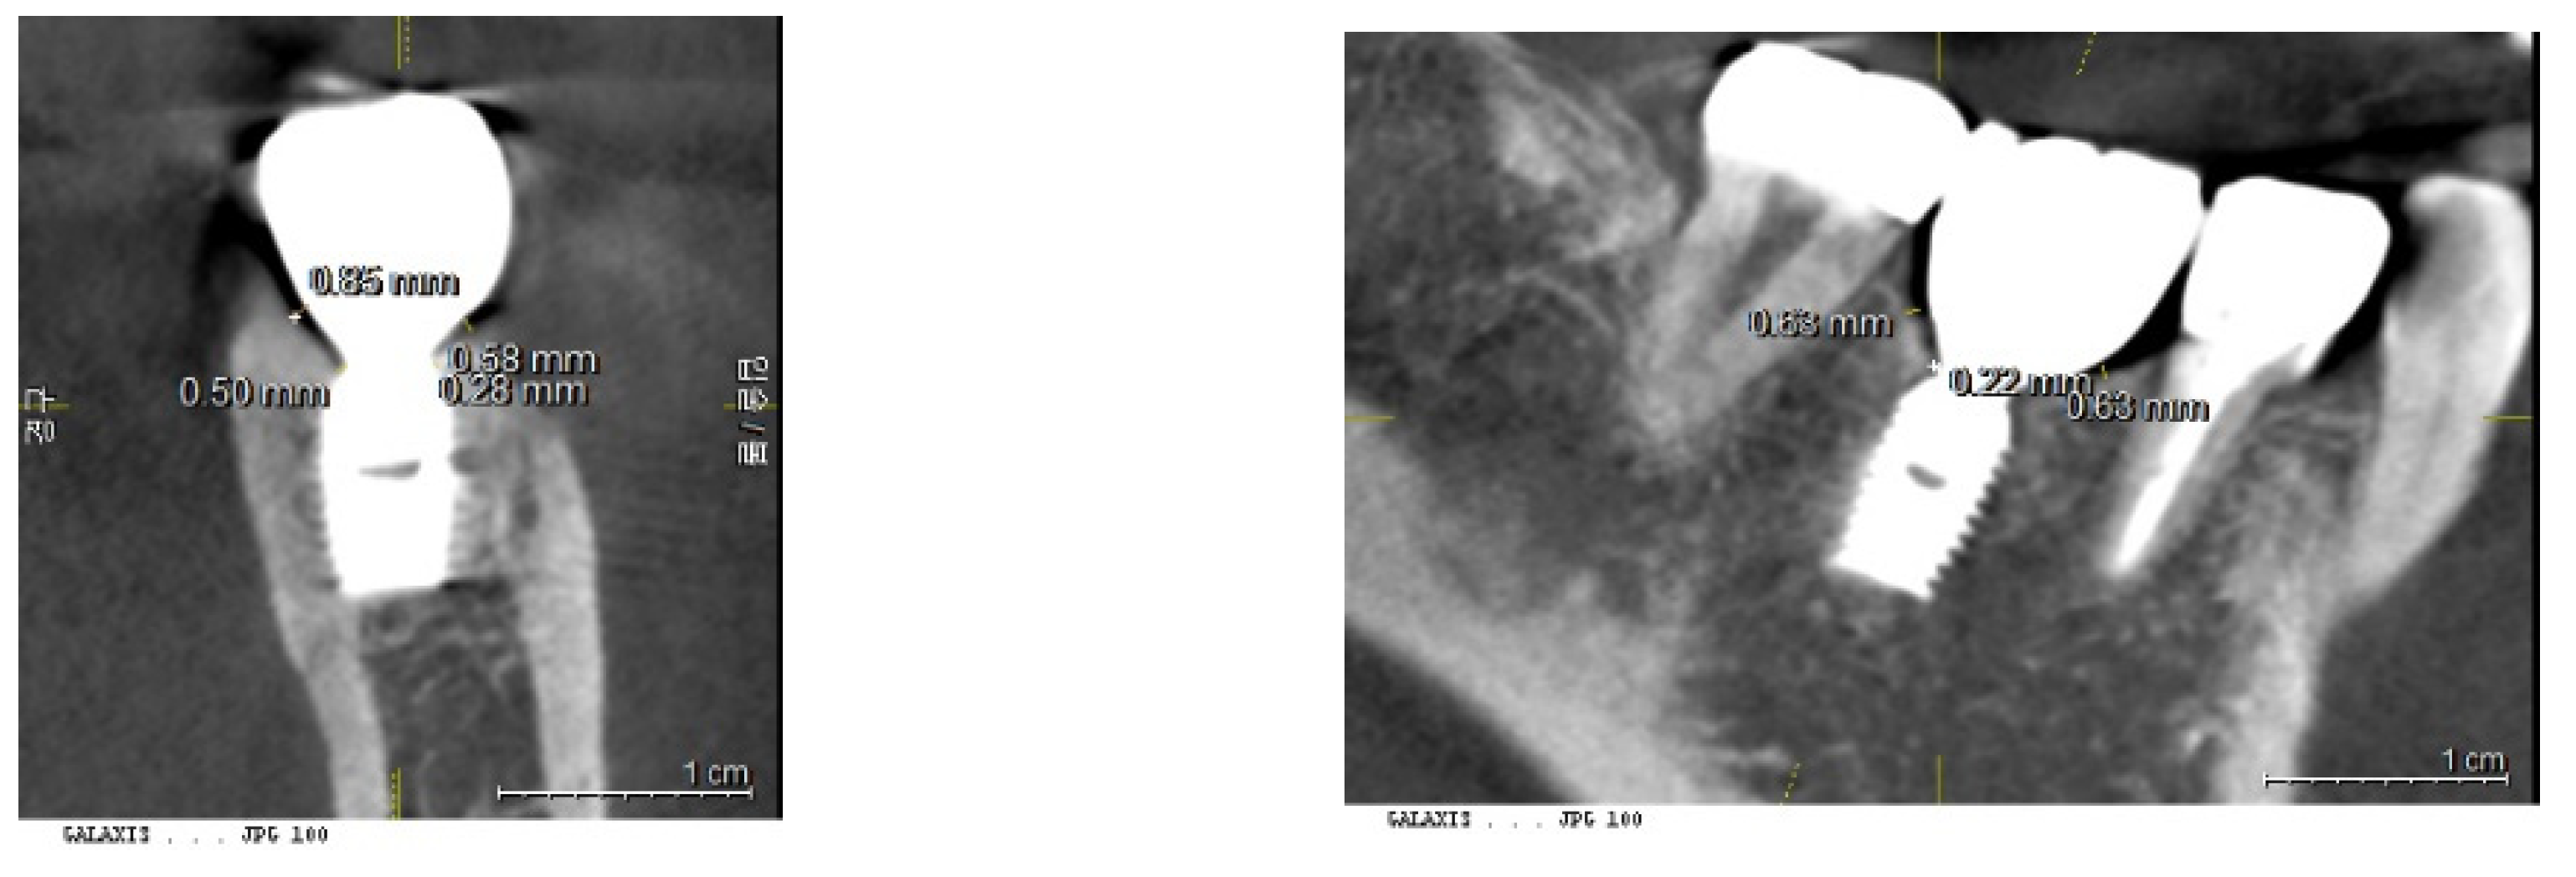

Calibration of CBCT: To ensure accuracy, the presentation plane of the CBCT was centered around the long axis of the fixture. This allowed for the confirmation of the fixture's size—both diameter and length—against its known original dimensions.

Figure 11. Calibration of CBCT Images. This figure demonstrates the calibration process where images are coordinated along the long axis of the fixtures. This alignment is crucial for accurate measurement and analysis, ensuring that the fixture dimensions are accurately reflected in the CBCT images.

2. Measurement of Placement Depth (PD) from CBCT - 3DSTA

Placement depth was assessed using CBCT in the 3DSTA context, focusing on both the central and peripheral areas in mesiodistal and buccolingual aspects:

a) Central Placement Depth (cPD): - The depth at the central area was measured as the perpendicular distance from the top point of the crestal bone to the platform of the implant fixture at its most outer point (e.g., at the 5 mm point of a 5 mm diameter fixture).

b) Peripheral Placement Depth (pPD) - Mesiodistal and Buccolingual Aspects: - In the mesiodistal aspect, the depth was measured as the perpendicular distance from the top point of the crestal bone to the platform of the implant fixture at the most outer point of the crown. - In the buccolingual aspect, the depth was measured from the most coronal top point of the crestal bone to the platform of the implant fixture.